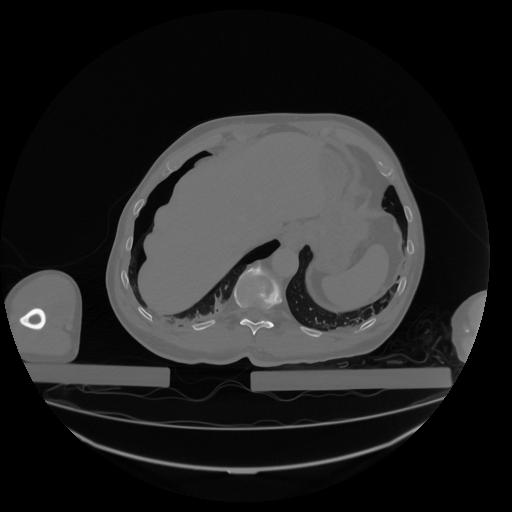

34 CUERPO,CE,Vol,1.0,CUERPO,,